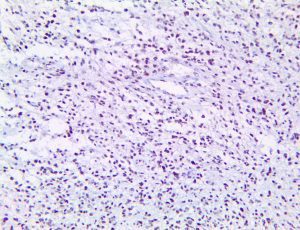

It is the ICU physician who is most likely to witness one of the deadliest manifestations of the abnormal immunological response, the cytokine storm syndrome (CSS). This response is also referred to by some as the cytokine release syndrome (CRS). CSS is characterized by continuous activation and expansion of macrophage and lymphocyte populations, which secrete large amounts of cytokines, causing the cytokine storm. This massive cytokine release is akin to hemophagocytic lymphohistiocytosis (HLH) disease, a syndrome characterized by initial unchecked and persistent activation of cytotoxic T lymphocytes and NK cells.

Clinical and laboratory manifestations of HLH include fever, enlarged liver and/or spleen, neurologic dysfunction, coagulopathy, liver dysfunction, cytopenias (i.e., low levels of erythrocytes, leukocytes, and/or platelets), hypertriglyceridemia, hyperferritinemia, hemophagocytosis, and eventually diminished NK cell activity as the immune system becomes progressively paralyzed. HLH can be familial (primary HLH) or secondary to another disease process (sHLH), such as rheumatic disease, in which it is referred to as macrophage activation syndrome (MAS, characterized by elevated ferritin).